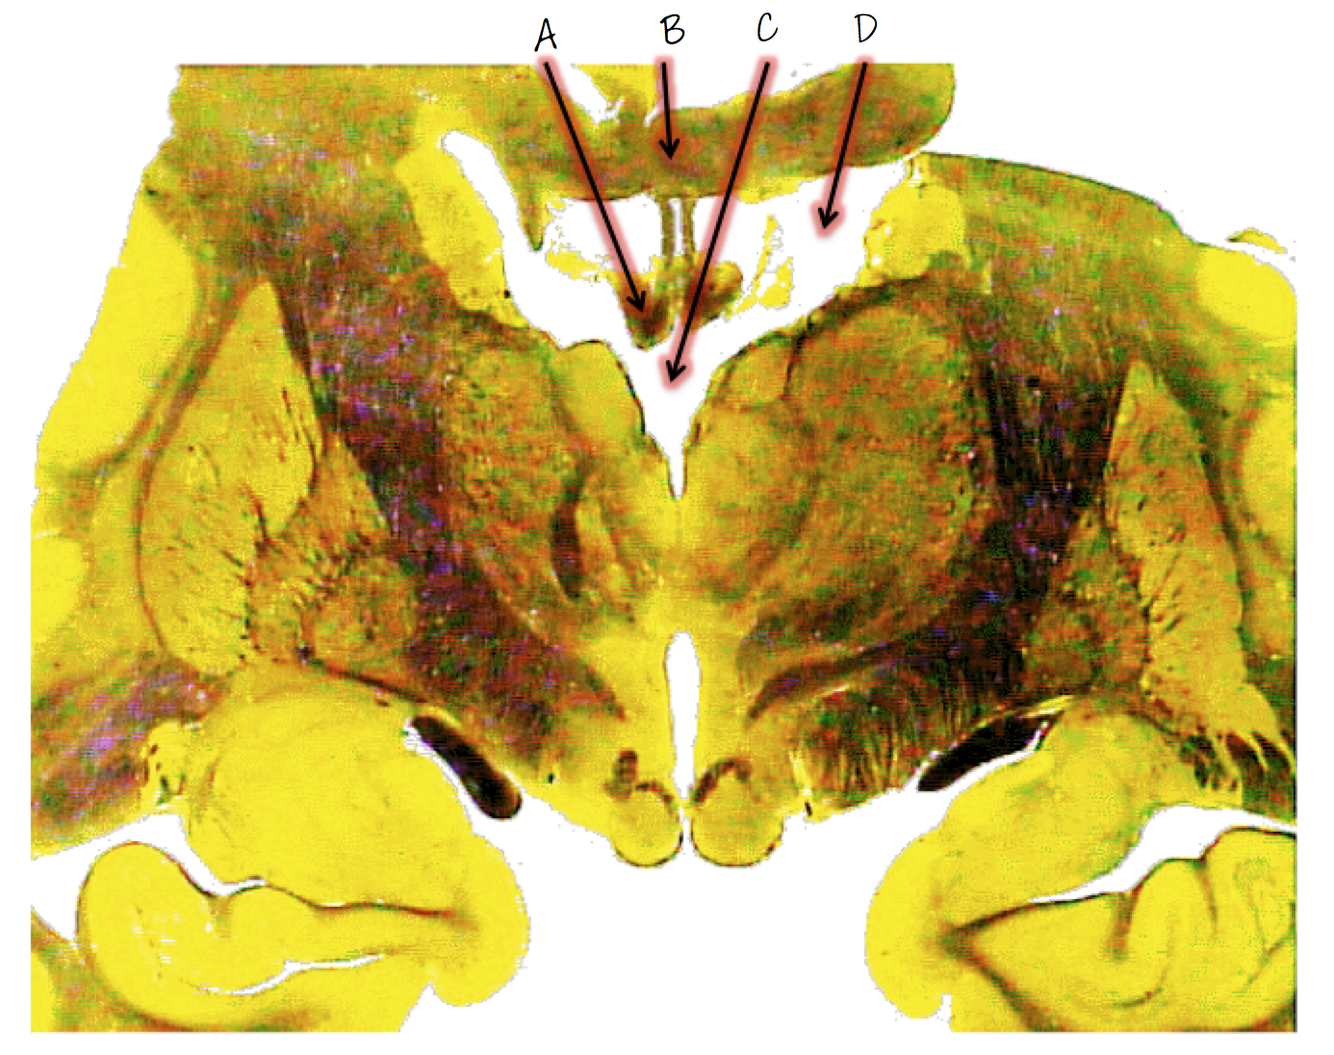

A; cerebral aqueduct

B; pineal body

C; oculomotor nucleus

D; periaqualdutal gray